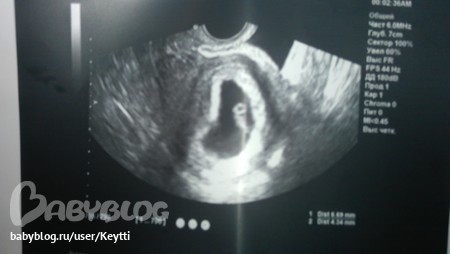

вот они долгожданные наши)))

первый

и второй )))

размер плода соответствует 6 неделям)) сердцебеение прослушивается у обоих))) так прям явно выраженно всё)))

КТР первого эмбриончика 7 мм, а второго 6 мм)))) ну и как такое возможно???))))